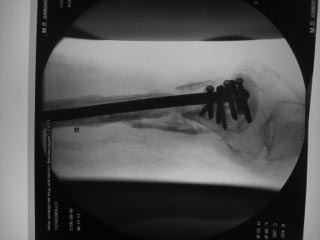

Пациентка 72 лет, сочетанная травма в июле 2011. Одно из повреждений (кроме ЧМТ, грудной клетки, длительной реанимации) перелом дистального бедра.

После временной фиксации в аппарате через 3 недели накостный остеосинтез. Раннее нагноение, попытки консеравативного лечения. Под наше наблюдение попала через 6 месяцев, гнойный свищ по наружной поверхности бедра, до пластины, нестабильная фиксация,миграция винтов, боли, постельный режим. Первым этапом удалена пластина, некрэктомия, бусы из цемента с а\б, апааратная фиксация. Заживление первичное. Вторым этапом снятие аппарта через месяц, замена бус, интрамедуллярный остосинтез, в последующем (через 1,5 месяца) бусы удалены, введены дополнительные винты из-за начинающейся миграции. Заживление первичное. В настоящее время 7 месяцев после последнего вмешательства, гвоздь динамизирован. На фоне улучшения общего состояния (пациенка активизирована, ходи с доп.опорой, болевой синдром незначительный) сохраняются эпизоды гипертермии проходящие на фоне а\б широкого спектра (авелокс). Р-граммы в динамике - отсутствие признаков нестабильности, резорбции, динамизация не исчерпана.Основная проблема - гипертермия, возобновляющаяся через 2-3 недели после прекращения а\б. Варианты:1) Наблюдать до 12-18 месяцев надесясь на консолидацию с последующим удалением 2) некрэктомия? 3) Резекция в пределах здоровых тканей с онкологическим протезом? Другие варианты